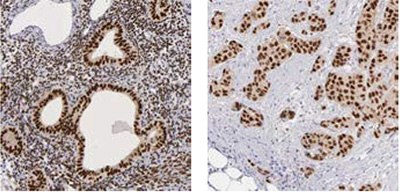

The IHC analysis using the Anti-RBM3 antibody HPA003624 showed a weak expression pattern in normal breast tissue, but a stratified pattern in breast cancer tissue (Figure 1). Researchers further investigated the expression in larger breast cancer cohorts and the expression of RBM3 was shown to be associated with a prolonged survival5.

Figure 1. Immunohistochemical analysis using the Anti-RBM3 antibody (HPA003624) shows weak expression in normal breast tissue (A) and differential expression, varying from weak to strong in tumor breast samples (B, C).